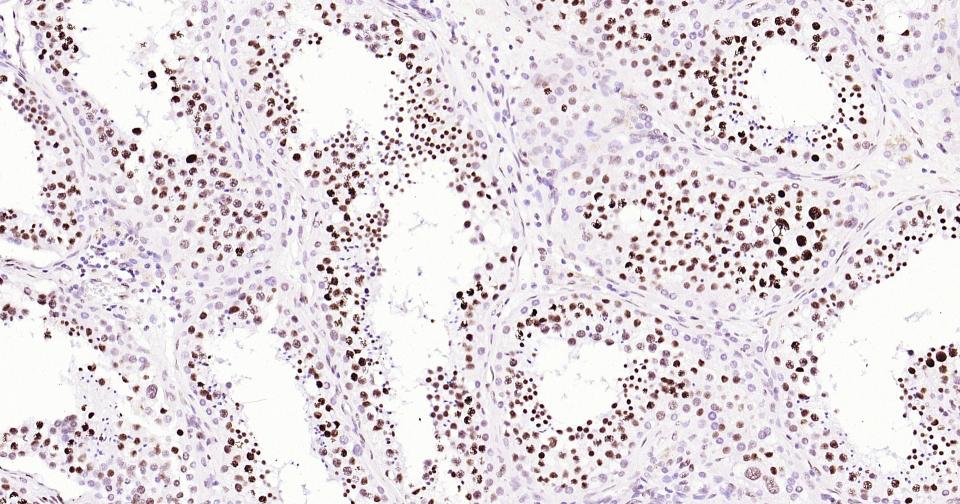

Histone H3 is one of the DNA-binding proteins found in the chromatin of all eukaryotic cells. H3 along with four core histone proteins binds to DNA forming the structure of the nucleosome. Histones play a central role in transcription regulation, DNA repair, DNA replication and chromosomal stability. Post translationally, histones are modified in a variety of ways to either directly change the chromatin structure or allow for the binding of specific transcription factors. The N-terminal tail of histone H3 protrudes from the globular nucleosome core and can undergo several different types of post-translational modification that influence cellular processes. These modifications include the covalent attachment of methyl or acetyl groups to lysine and arginine amino acids and the phosphorylation of serine or threonine.

用吸水纸吸去玻片上多余的液体,加入2-4滴大鼠Histone H3 鼠单抗工作液(试剂5),置于湿盒中,4℃孵育过夜或37℃孵育1-2 h。

*5. 发表论文时引用本产品的写作建议 "IHC0111R, Bioss Antibodies"。引用示例: “Rat tissue sections using Rat Histone H3 IHC Kit (IHC0111R, Bioss Antibodies) were stained for Histone H3 according to the manufacturer's instructions.”